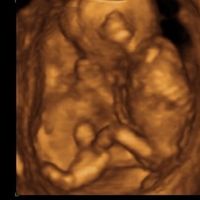

Hola guapas!!! Esta mañana he ido a mi doctora y me ha dicho que estoy de poquito, de 3 + 5... ¿De cuánto estábais cuando os hicisteis el test?